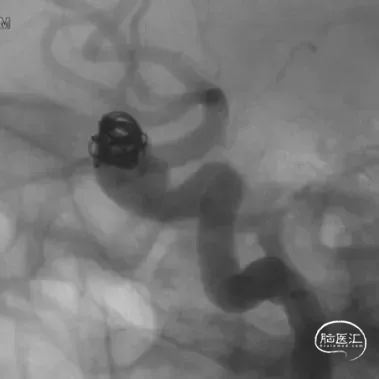

支架导管及弹簧圈微导管先后超选到位,其中弹簧圈微导管超选入远端眼动脉段动脉瘤内备用,根据测量结果,选用YonFlow®血流导向密网支架 4.5mm/30mm、弹簧圈9mm/40cm,先部分推出弹簧圈在动脉瘤内提供保护。再释放密网支架。

术后6个月造影随访提示动脉瘤完全愈合,载瘤动脉通畅。

4、该病例即刻造影显示血流重构满意,瘤腔内血流明显淤滞。术后六个月及12个月随访,均显示动脉瘤愈合,载瘤动脉通畅无狭窄。